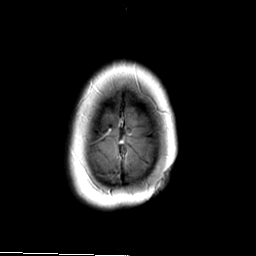

MR Study #3 -- Slice #48

[Home][Help][Clinical][Tour 1][Tour 2][Tour 3] Slice 48